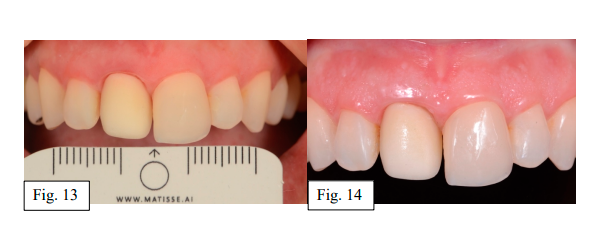

Com o auxílio do software DentalCad (Exocad), a estrutura e o desenho foram executados (TPD Paulo Caixeta). Considerando o desafio de mimetizar valor, matiz e saturação com a faceta pré-existente em cerâmica adjacente no dente 21, foi idealizado uma infraestrutura em Zircônia sobre aplicação de camada em e-max para obter substrato que oferecesse características semelhantes e melhorasse o prognóstico estético para cimentação de uma faceta, também em e-max press maquiada. Uma régua fotocromática com auxílio do software Matisse foi utilizada para identificar a cor e alcançar referências de semelhança entre os elementos 11 e 21 durante a prova da infraestrutura e da faceta (Fig. 13 e 14).